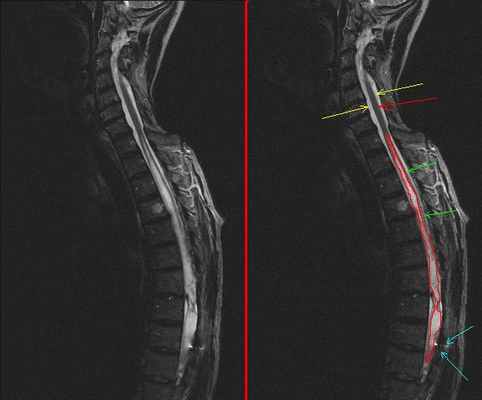

Точная диагностика возможна только с использованием МРТ спинного и головного мозга. Для получения нужной информации при исследовании используется контрастное вещество – гадолиний. Препарат, содержащий соли гадолиния, вводится внутривенно. Затем проводится МРТ головного или спинного мозга, выявляют наличие или отсутствие накопления контраста в патологических полостях, через некоторое время контрастное вещество выводится из организма естественным путем – с мочой.

Осмотр невролога может выявить потерю чувствительности или движение, вызванное компрессией спинного мозга. Диагноз обычно выставляется с помощью магнитно-резонансной томографии (МРТ) позвоночника, которая может подтвердить наличие сирингомиелии и определить точное местоположение кистозных образований и степень повреждения спинного мозга. Наиболее распространенным местом локализации кист является шейный отдел или же грудной отдел позвоночника. Наименее вероятным местом локализации кист является поясничный отдел позвоночника. МРТ головы может представлять диагностическую ценность для определения наличия каких-либо изменений таких как, например, гидроцефалия (избыток спинномозговой жидкости в желудочках мозга). При увеличении кистозных образований возможно возникновение деформации позвоночника (сколиоза), который хорошо диагностируется с помощью рентгенографии. Степень нарушения проводимости при сирингомиелии определяется с помощью ЭМГ.

Для выявления сирингомиелии пациент вначале проходит осмотр у невролога, а затем его направляют на магнитно-резонансную томографию (МРТ). Проведение этого вида исследования помогают выявить развитие патологии и с высокой точностью определить локализацию кистозных образований и степень повреждения спинного мозга.

- МРТ позвоночника и спинного мозга – наиболее надежный инструмент в диагностике сирингомиелии. Во время МРТ радиоволны и сильное магнитное поле используются для получения детальных изображений позвоночника и спинного мозга. В некоторых случаях применяется контрастное усиление – специалист вводит краситель в кровеносный сосуд, который по кровеносной системе подходит к позвоночнику и позволяет выявлять опухоли или другие его аномалии. МРТ периодически повторяют, это необходимо для контроля прогрессирования сирингомиелии.